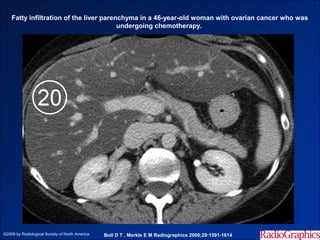

Fatty infiltration of the liver parenchyma in a 46-year-old woman with ovarian cancer who was

undergoing chemotherapy.

©2009 by Radiological Society of North America   Boll D T , Merkle E M Radiographics 2009;29:1591-1614

• #14 Fatty infiltration of the liver parenchyma in a 46-year-old woman with ovarian cancer who was undergoing chemotherapy. Sequential nonenhanced (a–c) and portal venous perfusion phase contrast material–enhanced (d–f) images from multidetector CT, obtained at 3-month intervals, show a progressive decrease in hepatic attenuation. Circle = region of interest, number = attenuation in Hounsfield units.

• #15 Fatty infiltration of the liver parenchyma in a 46-year-old woman with ovarian cancer who was undergoing chemotherapy. Sequential nonenhanced (a–c) and portal venous perfusion phase contrast material–enhanced (d–f) images from multidetector CT, obtained at 3-month intervals, show a progressive decrease in hepatic attenuation. Circle = region of interest, number = attenuation in Hounsfield units.